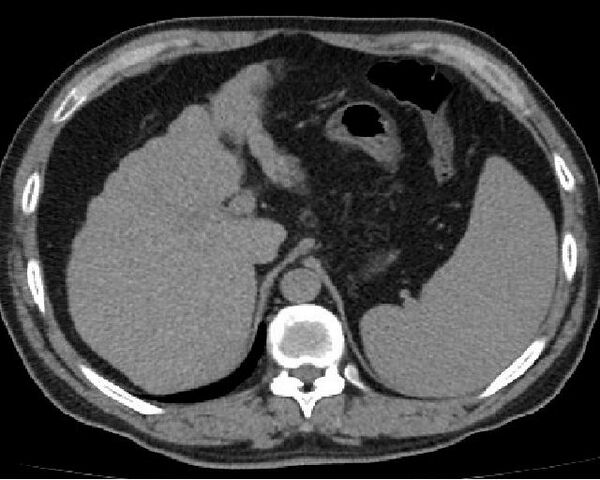

Печень увеличена или уменьшена в размерах, необычно плотная, бугристая, шероховатая. Десятилетняя смертность от постановки диагноза составляет 34—66 %, в зависимости от причин: алкогольный цирроз имеет худший прогноз, чем связанный с другими причинами. Первое известное описание заболевания было за авторством Гиппократа в 5 веке до нашей эры[2]. Сам термин «цирроз» был изобретён в 1819 году из-за желтоватого цвета больной печени[3].

Расширенные и извитые венозные коллатерали выявляются при ангиографии, компьютерной томографии, ультразвуковом исследовании или в ходе оперативного вмешательства.